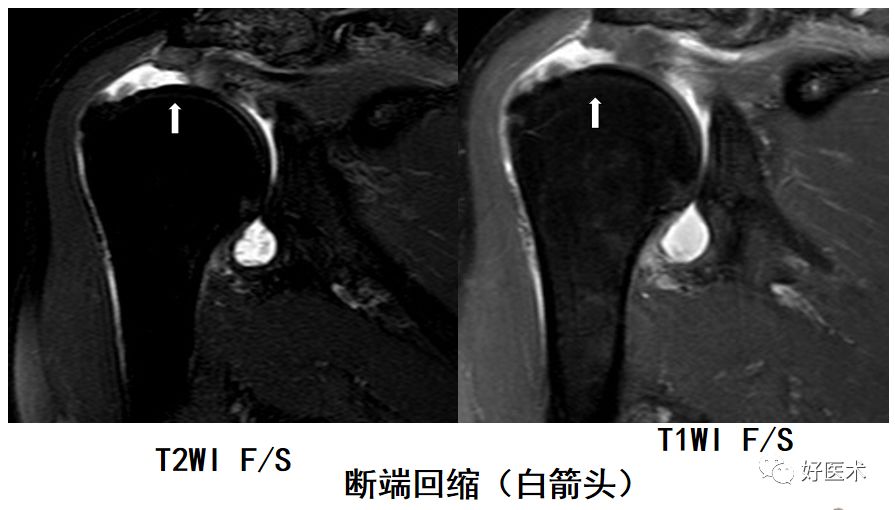

冈上肌完全撕裂

冈上肌全层撕裂伴肩撞(骨赘形成)

冈上肌全层撕裂MRI间接关节造影表现